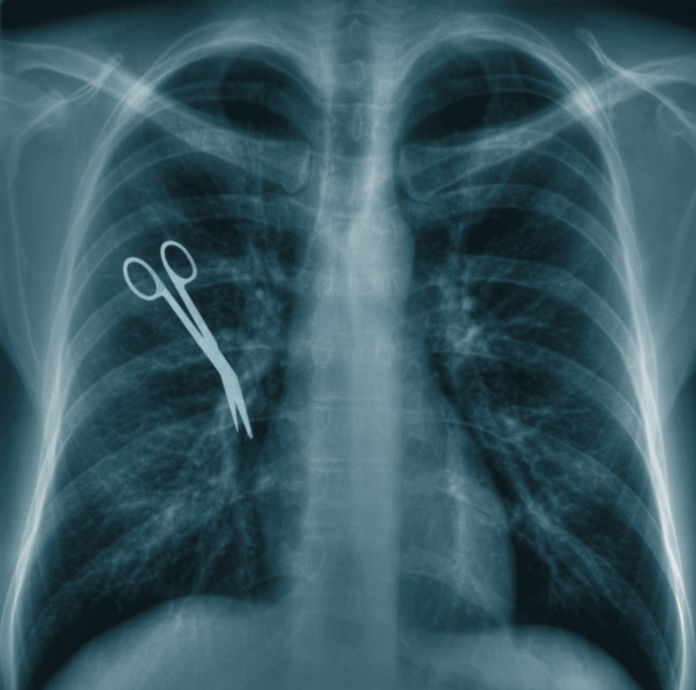

Surgical Tools Left Inside Patients. swabs and gauzes used during surgery or a procedure are one of the most common items left inside a patient, but surgical tools such as scalpels and drill bits have been found in some rare cases. the research showed that of the incidents of surgical instruments being wrongly left inside a patient, 68% were surgical packs, drain tubes or. retained surgical items, or retained foreign objects (rfos), are medical devices, tools, sponges, or instruments. it may happen rarely, but surgical items like sponges and scalpels are sometimes left inside of patients' bodies. cnn — two surgical sponges were left in a woman’s abdomen for at least six years, according to a new report in the new england journal of. nearly any object that comes into contact with a patient’s body has the potential to be left inside them, but the most common objects. one in six surgical instruments accidentally left inside a patient were not discovered for more than six months,.

cnn — two surgical sponges were left in a woman’s abdomen for at least six years, according to a new report in the new england journal of. the research showed that of the incidents of surgical instruments being wrongly left inside a patient, 68% were surgical packs, drain tubes or. it may happen rarely, but surgical items like sponges and scalpels are sometimes left inside of patients' bodies. retained surgical items, or retained foreign objects (rfos), are medical devices, tools, sponges, or instruments. nearly any object that comes into contact with a patient’s body has the potential to be left inside them, but the most common objects. one in six surgical instruments accidentally left inside a patient were not discovered for more than six months,. swabs and gauzes used during surgery or a procedure are one of the most common items left inside a patient, but surgical tools such as scalpels and drill bits have been found in some rare cases.

Surgical Tools Left Inside Patients one in six surgical instruments accidentally left inside a patient were not discovered for more than six months,. the research showed that of the incidents of surgical instruments being wrongly left inside a patient, 68% were surgical packs, drain tubes or. swabs and gauzes used during surgery or a procedure are one of the most common items left inside a patient, but surgical tools such as scalpels and drill bits have been found in some rare cases. retained surgical items, or retained foreign objects (rfos), are medical devices, tools, sponges, or instruments. it may happen rarely, but surgical items like sponges and scalpels are sometimes left inside of patients' bodies. one in six surgical instruments accidentally left inside a patient were not discovered for more than six months,. cnn — two surgical sponges were left in a woman’s abdomen for at least six years, according to a new report in the new england journal of. nearly any object that comes into contact with a patient’s body has the potential to be left inside them, but the most common objects.